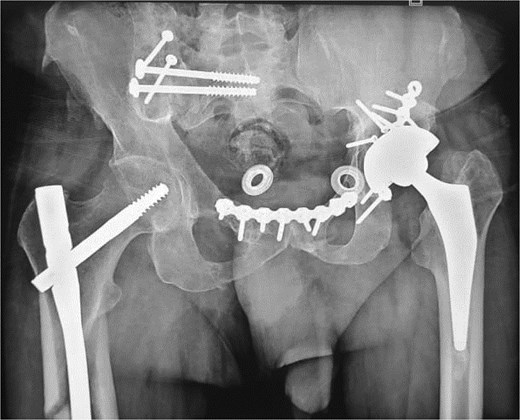

At the 10-month follow-up, the patient showed signs of left hip osteoarthritis with functional deterioration, for which a total ceramic-on-ceramic hip arthroplasty was performed, using a screw-fixed structural graft at the acetabulum (Fig. 3). At the final follow-up, 36 months postoperatively, the patient was walking unaided with the use of an anti-equinus splint on the left foot. The HHS was 85 and Majeed score was 86 [6, 7]. X-rays showed complete bone healing of all fractures and the acetabular graft. It should be noted that, during follow-up, the patient had a right femoral fracture that was successfully treated with a gamma nail (Fig. 4). Written informed consent were obtained from the patient.

(a and b) Inlet and obturator oblique views showing a left hip osteoarthritis with subluxation of the femoral head. (c) Anteroposterior pelvic X-ray: left total hip arthroplasty, acetabular bone reconstruction with a screwed structural bone graft.